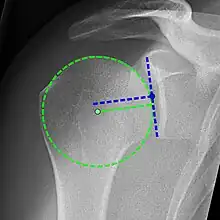

Projectional radiograph of normal glenohumeral position.[51]

High-riding humeral head in a rotator cuff tear.

X-ray projectional radiography cannot directly reveal tears of the rotator cuff, a 'soft tissue', and consequently, normal X-rays cannot exclude a damaged cuff. However, indirect evidence of pathology may be seen in instances where one or more of the tendons has undergone degenerative calcification (calcific tendinitis). The humeral head may migrate upward (high-riding humeral head) secondary to tears of the infraspinatus, or combined tears of the supraspinatus and infraspinatus.[51] The migration can be measured by the distance between:

• A line crossing the center of a line between the superior and inferior rims of the glenoid articular surface (blue in image).

• The center of a "best-fit" circle positioned over the humeral articular surface (green in image)

Normally, the former is positioned inferiorly to the latter, and a reversal therefore indicates a rotator cuff tear.[51] Prolonged contact between a high-riding humeral head and the acromion above it may lead to X-ray findings of wear on the humeral head and acromion; secondary degenerative arthritis of the glenohumeral joint (the ball and socket joint of the shoulder), called cuff arthropathy, may follow.[50] Incidental X-ray findings of bone spurs at the adjacent acromioclavicular joint may show a bone spur growing from the outer edge of the clavicle downward toward the rotator cuff. Spurs may also be seen on the underside of the acromion, once thought to cause direct fraying of the rotator cuff from contact friction, a concept currently regarded as controversial.